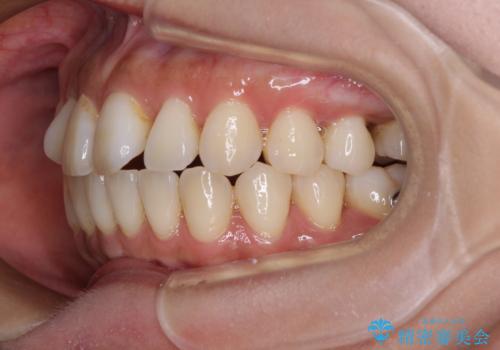

【モニター】上顎前突と奥歯の鋏状咬合 補助装置を用いたインビザライン矯正治療

- 前歯の歯列不正と奥歯の咬みにくさを気にして来院された患者様です。

インビザラインでの矯正治療を希望されていましたが、奥歯の咬み合わせがインビザライン単独では改善困難と判断されたので、補助装置を併用することとしました。

上顎最後臼歯は極端に外側を向いており、下顎骨に対して上顎骨が前方に位置していたため、補助装置により最後臼歯を一気に内側に引き込むとともに、上顎臼歯を後方移動させ、奥歯の咬み合わせが改善した後に、上下インビザラインにより歯列全体を整えていくこととしました。

奥歯の咬み合わせを事前に望ましい位置に改善したことで、インビザライン単独では改善が最も困難な状況を排除することができ、非常に理想的な仕上がりとなりました。